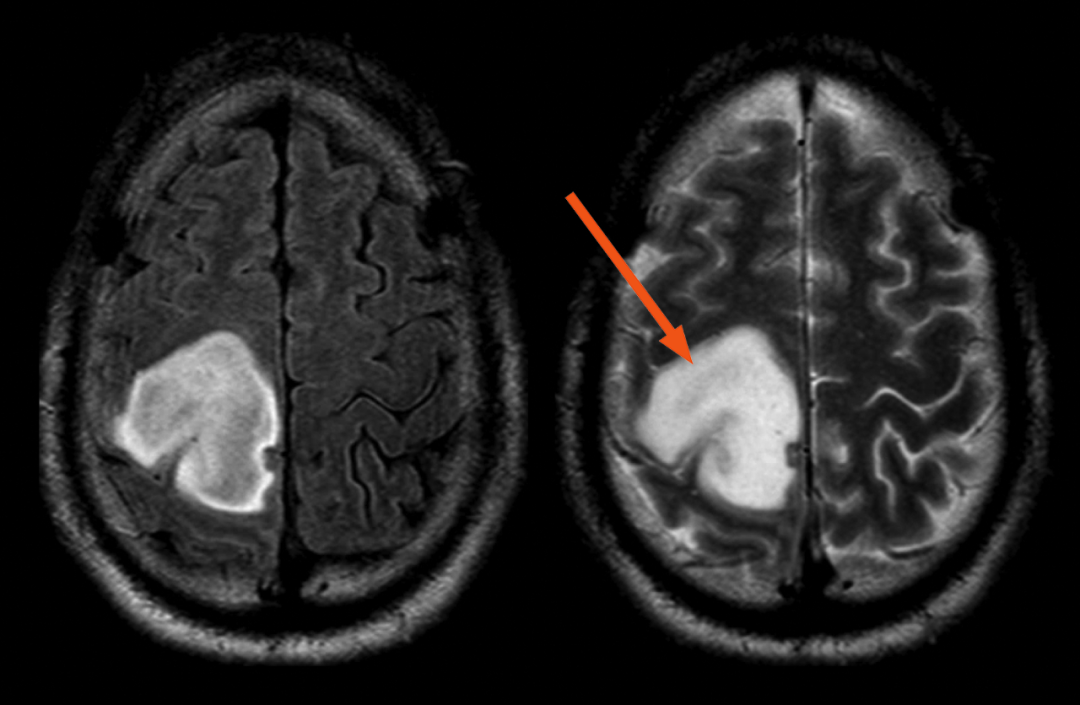

尽管肿瘤相对于 T2WI 在 FLAIR 序列上包含小的低信号区域(箭头),但大部分占位在 FLAIR 上显示的信号类似于 T2WI,不符合 T2-FLAIR 错配

肿瘤 T2WI 高信号不均质,不符合 T2-FLAIR 错配

2)T2WI 肿瘤内包被的皮质灰质可能显示相对低信号,此发现不应排除 T2-FLAIR 错配的迹象

包被的皮质灰质